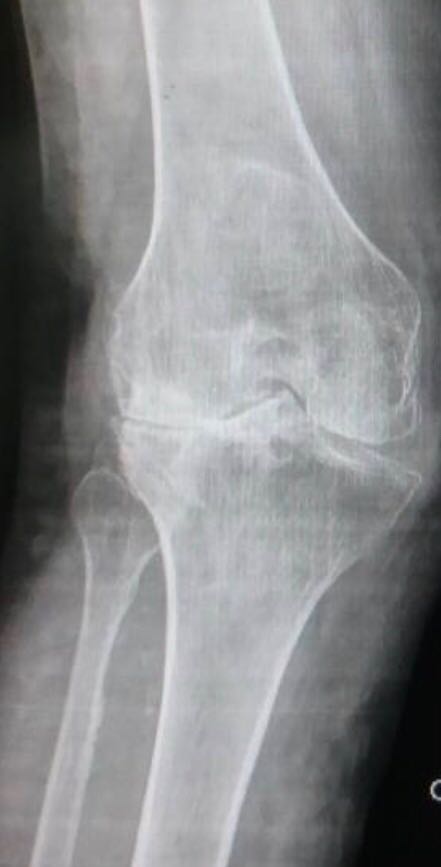

Cliquer sur une photo pour défiler la collection1- Gonarthrose sur Genu valgum

1- Gonarthrose sur Genu valgum